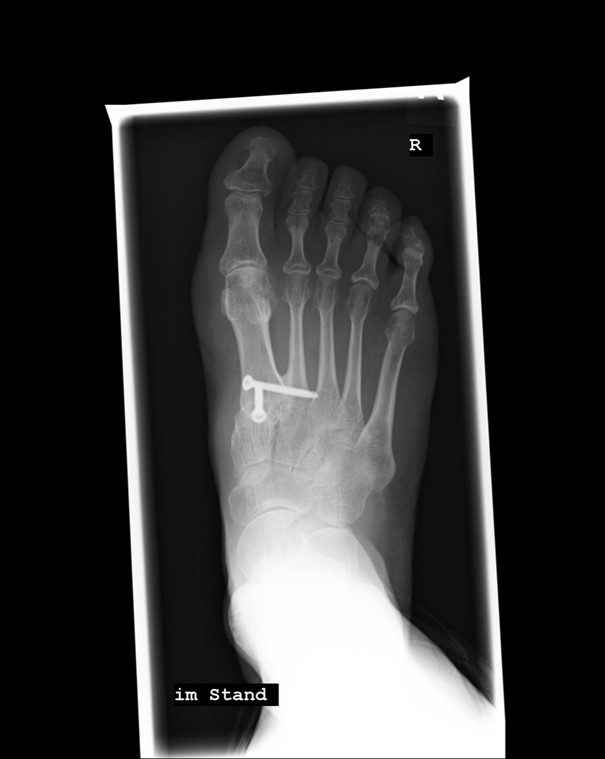

- Arthrodese nach Lapidus: Versteifung der Fußwurzel und des Mittelfußknochens am ersten Fußstrahl (Großzehe) unter Einbezug des zweiten Mittelfußknochens. Das erste Gelenk (zwischen Fußwurzelknochen I und Mittelfußknochen I) wird weggenommen. Ein Teil des Mittelfußknochens wird präpariert, um das Mittelfußgelenk wieder in eine gerade Position zu bringen. Diese neue Position wird mit Schrauben fixiert. Es wird eine Verknöcherung von drei Knochen erreicht: erster und zweiter Mittelfuß- und erster Fußwurzelknochen. Diese artikulieren danach “en bloc” mit der Fußwurzel in einem neuen, mehrfach verwinkelten und dadurch stabilen Gelenk mit dem Rest der Fußwurzel.

- Im Anschluss wird die Diagnose meist durch eine Röntgenaufnahme unter Belastung bestätigt. Durch dieses bildgebende Verfahren kann die Ausprägung der Fehlstellung unter anderem durch Ermittlung des IMR-I-Winkels (siehe oben) und der Instabilität beurteilt werden.

Mit einer Lapidusarthrodese wird nicht nur das TMT I Gelenk versteift, sondern auch eine zusätzliche Fusion zwischen Mittelfußknochen I und II erreicht. Dieses Gelenk stellt häufig eine Schwachstelle der gesamten Fußgewölbe-Konstruktion dar. Die evolutionsbedingte gelenkige Verbindung an dieser Stelle kann horizontale und vertikale Instabilitäten verursachen. Die Vorteile einer Lapidus Arthrodese liegen eindeutig darin, dass man die Ursache der atavistischen Fehlstellung der auseinander gespreizten Mittelfußknochen und dabei ganz nebenbei das Symptom “Hallux valgus“ am Fuß beseitigt. Nur hierdurch kann das OP-Ergebnis nachhaltig werden.